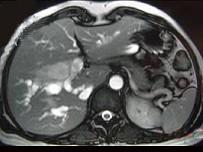

问题 女,35岁,右上腹痛1月,黄疸进行性加重,AFP阴性,消瘦乏力,影像检查如图,最可能的诊断为()

选项 A.肝转移癌 B.胆管癌 C.局灶性脂肪肝 D.原发性肝癌 E.肝血管瘤

答案 B